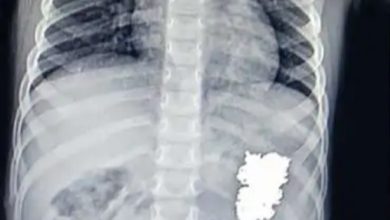

മൂന്നര വയസുള്ള കുട്ടിയുടെ വയറ്റിൽ നിന്നും അരഞ്ഞാണം പുറത്തെടുത്തു

പാലാ: മൂന്നര വയസുള്ള കുട്ടി അബദ്ധത്തില്‍ വിഴുങ്ങിയ അരഞ്ഞാണം പാലാ മാര്‍ സ്ലീവാ മെഡിസിറ്റിയിലെ ഡോക്ടര്‍മാരുടെ നേതൃത്വത്തില്‍ പുറത്തെടുത്തു. പള്ളിക്കത്തോട് സ്വദേശികളായ ദമ്ബതികളുടെ പെണ്‍കുഞ്ഞാണ് വെള്ളി അരഞ്ഞാണം വിഴുങ്ങിയത്. കഴിഞ്ഞ ദിവസം രാത്രി വീടിനുള്ളില്‍ കളിക്കുന്നതിനിടെ അരയില്‍നിന്ന് ഊരിപ്പോയ അരഞ്ഞാണം അബദ്ധത്തില്‍ വിഴുങ്ങുകയായിരുന്നു. തുടര്‍ന്നു കുഞ്ഞ് അസ്വസ്ഥത പ്രകടിപ്പിച്ചു. ഇതിനിടെ വീട്ടുകാര്‍ നോക്കിയപ്പോള്‍ അരഞ്ഞാണം നഷ്ടപ്പെട്ടിരിക്കുന്നതായി ശ്രദ്ധയില്‍പ്പെട്ടു. ഉടന്‍തന്നെ മാര്‍ സ്ലീവാ മെഡിസിറ്റിയിലെ അത്യാഹിത വിഭാഗത്തില്‍ എത്തിക്കുകയും ഡോ. വിപിന്‍ ലാലിന്‍റെ നേതൃത്വത്തില്‍ എക്‌സ്‌റേ എടുത്തു നടത്തിയ പരിശോധനയില്‍ അരഞ്ഞാണം വയറിനുള്ളില്‍ കുടുങ്ങിക്കിടക്കുന്നതായി കണ്ടെത്തുകയും ചെയ്തു. ഉടന്‍തന്നെ ഗാസ്‌ട്രോഎന്‍ററോളജിസ്റ്റ് ഡോ. പ്രിജിത്ത് ഏബ്രഹാം തോമസ്, അനസ്‌തെറ്റിസ്റ്റുകളായ ഡോ. ലിബി ജി. പാപ്പച്ചന്‍, ഡോ. സേവ്യര്‍ ജോണ്‍ എന്നിവരുടെ നേതൃത്വത്തില്‍ കുഞ്ഞിനെ എന്‍ഡോസ്‌കോപ്പിക്കു വിധേയയാക്കി. തുടര്‍ന്നു സുരക്ഷിതമായി വയറ്റില്‍നിന്ന് അരഞ്ഞാണം പുറത്തെടുത്തു. കുഞ്ഞിന്റെ ആരോഗ്യനില തൃപ്തികരമാണെന്ന് ഡോക്ടർമാർ അറിയിച്ചു.